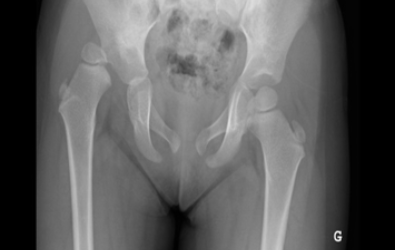

The x-ray shows a hip arthrography

performed by Dr. Zenios.

The x-rays show cases of developmental dysplasia of the in the hips that presented after the age of three years. The patients underwent surgery by Dr. Zenios for hip reduction with a pelvic and femoral osteotomy.